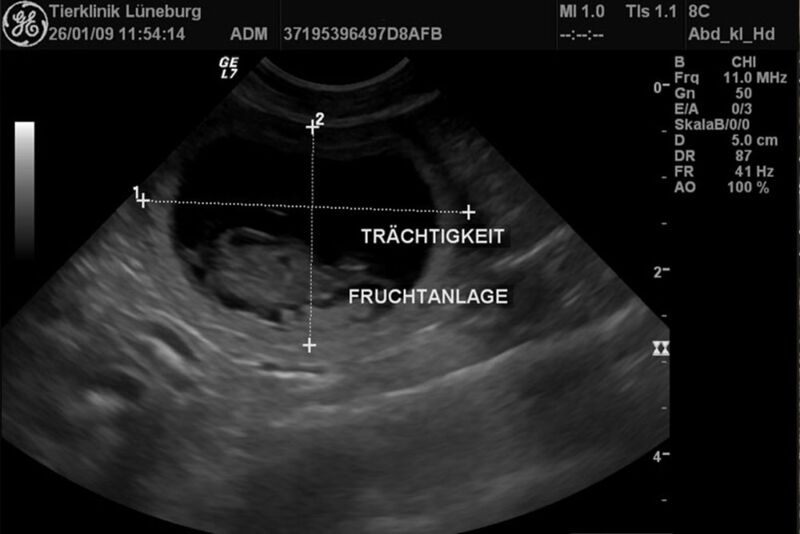

Durch unsere hochauflösenden Ultraschallgeräte können wir ab dem 21. Tag der Trächtigkeit den Fetus und dessen Herzschlag im Dopplerverfahren darstellen.